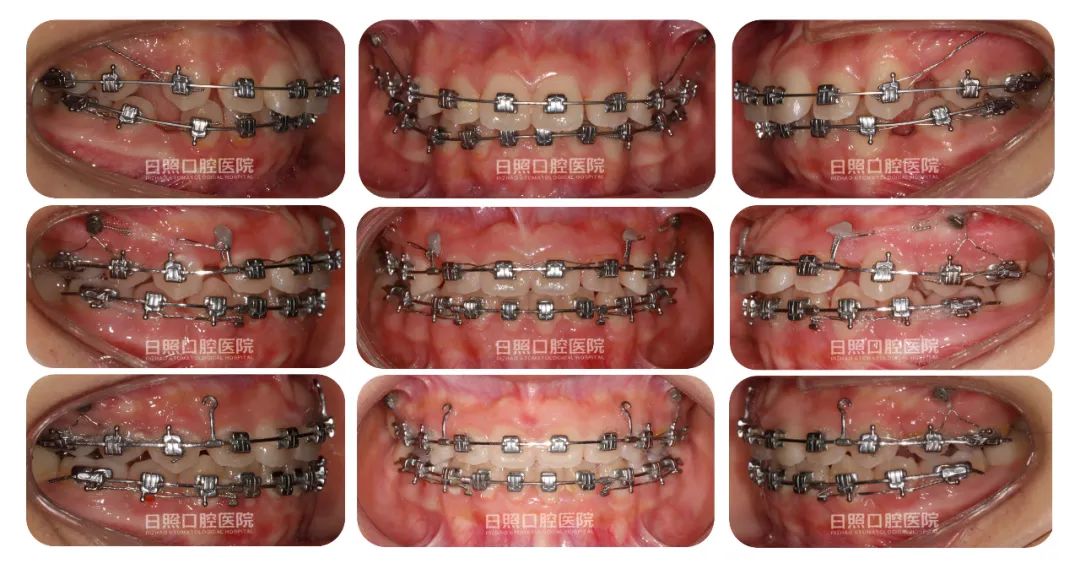

治疗中口内照

治疗后口内照